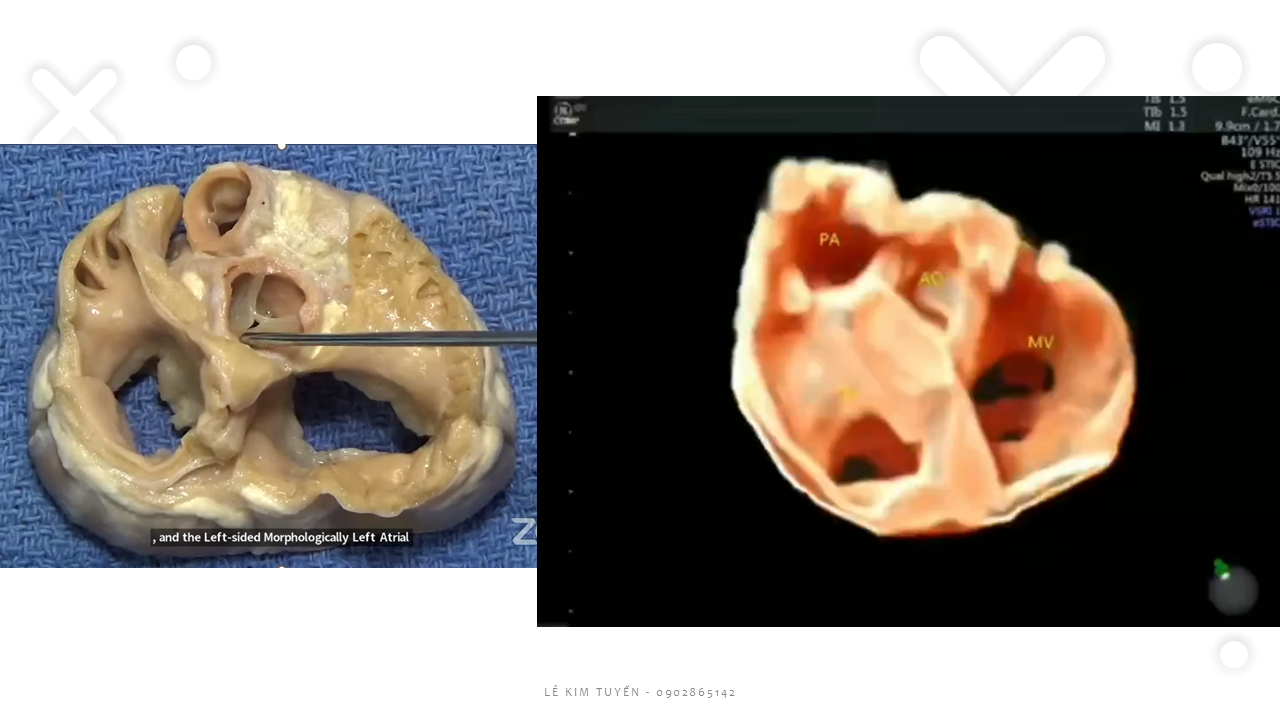

Siêu âm tim thai - Các kỹ thuật hiện đại

TS. BS. Lê Kim Tuyến